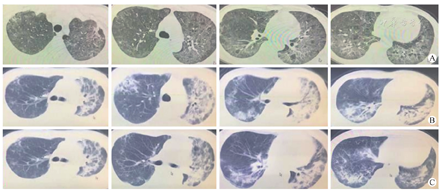

例1 男性,48岁,终末期肾病,原发病为高血压肾病。既往史:高血压病多年,2019年9月16日行器官捐献供肾移植,免疫诱导方案:甲泼尼龙+巴利昔单抗(20 mg,术中)+抗人类胸腺细胞免疫球蛋白(ATG,25 mg/d,术后3~5 d),免疫维持方案:霉酚酸+他克莫司+激素三联用药,术后肾功能恢复良好,血肌酐维持在120~160 μmol/L。2019年12月前在武汉居住随访,12月前往广东生活,1月5日起逐渐出现发热、咳嗽,伴活动后胸闷、乏力。2020年1月15日入院,查血常规+超敏C反应蛋白+血清淀粉样蛋白A:白细胞11.58×109/L ,中性粒细胞计数10.74×109/L,淋巴细胞计数0.34×109/L,血红蛋白106 g/L,C反应蛋白90 mg/L,血清淀粉样蛋白A>300 mg/L;细胞免疫:CD4计数225/μL,CD8计数111/μL;肾功能:尿素氮(BUN) 18.35 mmol/L,血肌酐(Cr) 214.00 μmol/L,呼吸道病原抗体定性(9种):阴性,半乳甘露聚糖试验阴性,1,3-β-D葡聚糖试验42.84 ng/L,巨细胞病毒DNA定量(全血):7.49×103拷贝数/ml。肺部CT提示双肺广泛渗出的毛玻璃样影,伴纤维条索影(图1A)。诊断:肾移植术后,肾功能不全;间质性肺炎,病毒性肺炎?治疗方案:停用免疫抑制剂,予以丙种球蛋白(10 g/d,肌内注射);奥司他韦(150 mg/d,一日2次);复方磺胺甲恶唑片(8片/d,一日4次);更昔洛韦(500 mg/d,一日2次);甲泼尼龙(80 mg/d,一日2次);亚胺培南抗G-菌,米卡芬净抗真菌治疗。治疗1周后受者发热、胸闷症状稍缓解,生命体征稳定,低流量吸氧下(2 L/min)指脉氧饱和度92 %以上。1月22日进行鼻咽拭子2019-nCoV核酸检测提示阳性,考虑新发COVID-19。立即予以单间隔离,三级防护,后转入定点医院治疗。治疗方案包括停用免疫抑制剂,头孢哌酮钠舒巴坦钠+利奈唑胺抗感染,丙种球蛋白提升免疫功能,甲泼尼龙抗炎症反应,抗病毒方案为:阿比多尔(0.6 g/d,一日3次);洛匹那韦利托那韦片(1.0 g/d,一日2次)。

例1目前追踪3周,精神状态可,无发热,活动后仍喘气,肺部CT检查显示稍吸收(图1B、图1C),但肾功能受损,2月6日血肌酐265 μmol/L,2月9日血肌酐706 μmol/L,尿量600~1500 ml/d,密切接触者无2019-nCoV感染者。

2019-nCoV最初的传染源仍不明确,目前比较倾向于蝙蝠,可能经过中间宿主传播给人类,目前所见传染源主要是COVID-19患者[2]。传播途径包括经呼吸道飞沫传播和接触传播[2]。人群普遍易感,老年并伴有糖尿病等基础疾病者易出现重症,儿童婴幼儿也有发病[2]。潜伏期一般3~7 d,不超过14 d。目前报道的2019-nCoV毒力较SARS弱,死亡率在5 %左右,但传染性较强,感染后临床表现多样,包括呼吸道症状、消化道症状[2],在免疫缺陷人群中,可有不典型或无症状的表现。COVID-19的临床表现同巨细胞病毒(CMV)肺炎、流感病毒肺炎、腺病毒肺炎类似,包括发热,咳嗽,喘气等。COVID-19早期影像学表现为间质性肺炎,同其他病毒性肺炎类似,但也有一定差别,COVID-19主要是表现在单侧或双侧肺部局限性炎症浸润,以胸膜下斑片状,团块状,节段或亚段磨玻璃影多见;CMV肺炎为双侧弥漫性分布不对称磨玻璃影,界限不清的小结节和实变;流感病毒性肺炎为沿支气管血管束的多个不规则实变区域和弥漫性磨玻璃影,到进展期以及恢复期各种病毒性肺炎影像学表现形式多种多样不易鉴别[3]。例1影像学并不符合典型的COVID-19表现,考虑受者前期CMV肺炎,后期被传染继发了COVID-19,经过药物治疗后期的影像学形态多样。例2并未进行CT诊断。COVID-19最终确诊仍需依赖2019-nCoV核酸检测,目前临床上主要使用鼻咽拭子做2019-nCoV核酸检测,由于取材方法的差异,以及不是在病变部位的样本容易出现假阴性,导致临床漏诊,延误治疗,2019-nCoV核酸检测是否会出现假阳性目前没有报道[4]。目前多强调诊断结合临床症状,影像学结果和2019-nCoV核酸检测综合诊断,例1有典型临床表现,2019-nCoV核酸检测结果阳性,但由于前期伴发CMV感染,并且经过治疗后影像学不典型,综合考虑为COVID-19。例2虽出现了一过性发热,鼻咽拭子2019-nCoV核酸检测阳性,但无明确影像学证据,后期2019-nCoV核酸很快转阴,因此考虑为2019-nCoV感染但未出现COVID-19。目前指南认为2019-nCoV感染出现的临床综合征包括单纯性感染、轻症肺炎、重症肺炎、急性呼吸窘迫综合征、脓毒症、脓毒症休克等[5],因此2019-nCoV感染的表现形式多种多样需引起临床警惕。针对2019-nCoV目前没有特效抗病毒药物,指南推荐可试用α-干扰素雾化吸入、洛匹那韦/利托那韦或可加用利巴韦林[2]。例1选择了阿比多尔+洛匹那韦利托那韦片抗病毒治疗,例2只选择了阿比多尔抗病毒治疗,其余为对症支持治疗,包括控制炎症反应、氧疗、提升免疫功能、营养支持。目前有病例报道阿比多尔、干扰素、雷米迪维或瑞德西韦(Remdesivir)、氯喹(Chloroquine)、利托那韦(Ritonavir)能够治疗2019nCoV[6],美国利用瑞德西韦抗病毒也显示出良好的治疗效果[7],也有研究表明传统中药疏风解毒胶囊和连花清瘟胶囊等具有一定效果,但都缺乏大规模多中心临床研究证实[6]。肾移植受者作为免疫低下人群,理论上更易感,但目前了解武汉市四家移植中心感染发生率并不高,仍需进一步流行病学调查[8]。面对COVID-19暴发流行现状,重点是要做好预防措施,包括戴口罩,勤洗手,居家隔离,少聚餐,避免暴露在具有传染源环境中,做好居住环境的通风消毒。建议肾移植受者在肾功能稳定,尿量正常情况下延迟1~2周复查,通过网络查询检验结果,进行网络问诊,调整药物剂量。出现急症必须去医院诊治时,做好个人防护,不要延误治疗,也不要自行减少免疫抑制剂剂量。如果出现相关呼吸道症状及时前往发热门诊就诊,按照国家卫生健康委员会颁布的指南选择相应的诊疗方案[2]。